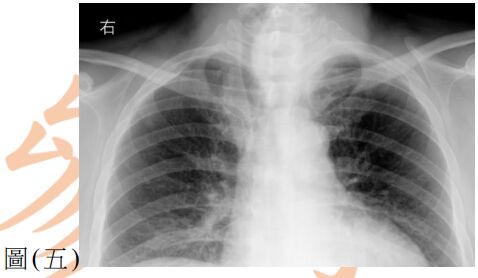

38. 病人接受甲狀腺全切除手術前的胸腔X光片如圖(五) ,下列敘述何者最適當?

(A) 氣管位置向右偏移 (B) 氣管與甲狀腺間有沾黏 (C) 氣管與血管間有廔管 (D) 氣管發育不全